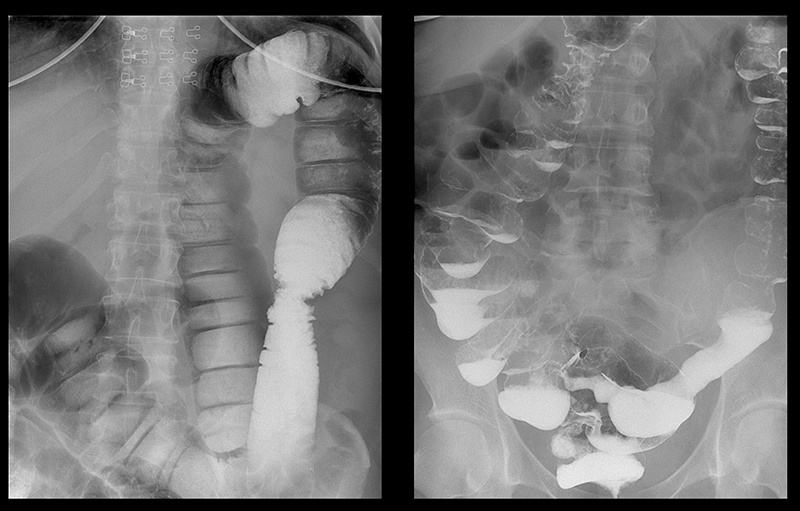

Подивіться знімки органів людей, у яких усе почалося з неприємного запаху з рота, закрепів та печії, а закінчилося доповіддю патологоанатома.

‘’Рак товстої кишки у жінки зі скаргою на часті закрепи’’

‘’Рентгенографія калового каміння в товстій кишці’’

‘’Стадії раку прямої кишки які формуються протягом 1-2 років’’